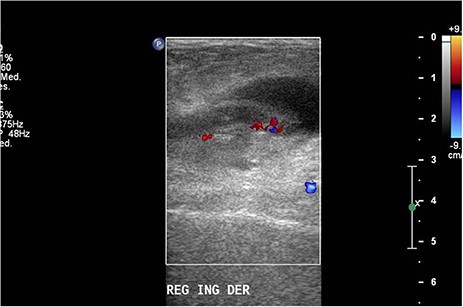

Ultrasound was performed with a Philips iU22 ultrasound using a 9 MHz linear transducer. A well-defined cystic mass was observed over the area. Right in the middle, a tubular image that terminated in a blind-ended tip in the longitudinal plane (Fig. 1A) and a target appearance on the cross-sectional plane (Fig. 1B) consistent with the appendix were demonstrated. The appendix measured 0.63 and 0.72 mm, discreetly above normal range, and it showed hypoechoic thickening of the mucosal layer. Color Doppler flow of the tip (Fig. 2) and adjacent soft tissue showed inflammatory changes. The patient presented pain on compression with the transducer. The surrounding fat tissue presented increased echogenicity suggesting inflammatory tissue. The preoperative surgical diagnosis was a strangulated inguinofemoral hernia. However, the findings were reported as acute appendicitis within an inguinal hernia sac. Inguinal hernioplasty with inguinal exploration and repair of an inguinofemoral hernia and resection of intestinal contents were performed (Fig. 3).

(A) Longitudinal ultrasound of the groin area showing a well-defined cystic mass with a central tubular image that terminated in a blind-ended tip. (B) Cross-sectional ultrasound showing the appendix more than 6 mm in diameter with echogenic surrounding fat soft tissue suggesting inflammatory changes.

Doppler ultrasound with increased flow on the tip of the appendix.